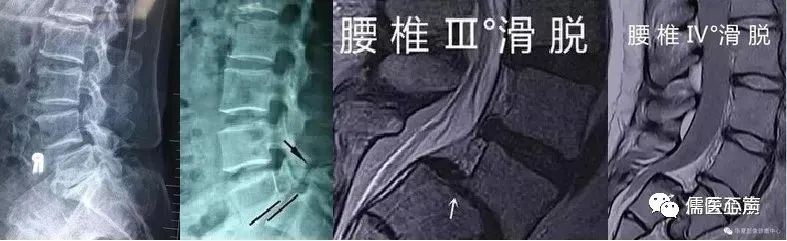

腰椎滑脱的影象学改变有哪些呢?

1、 X线片表现①前后位片:不易显示峡部病变。通过仔细观察,可能发现在椎弓根阴影下有一密度减低的斜行或水平裂隙,多为双侧,宽度约1~2 mm。明显滑脱的患者,滑脱的椎体因与下位椎体重叠而显示高度减小,椎体倾斜、下缘模糊不清、密度较高,与两侧横突及骶椎阴影相重叠,称为Brailsford弓。滑脱腰椎的棘突可向上翘起,也可与下位椎体之棘突相抵触,并偏离中线。②侧位片:能清楚显示椎弓崩裂形态。裂隙于椎弓根后下方,在上关节突与下关节突之间,自后下斜向前下,边缘常有硬化征象。病变一侧者侧位片显示裂隙不完全或不清楚,两侧者显示较清楚。侧位片可显示腰椎滑脱征象,并能测量滑脱分度及分级。

腰椎滑脱的分级。

国内常用的是Meyerding分级,即将下位椎体上缘分为4等份,根据椎体相对下位椎体向前滑移的程度分为I-IV度。Ⅰ:指椎体向前滑动不超过椎体中部矢状径的1/4者。Ⅱ :超过1/4,但不超过2/4者。Ⅲ :超过2/4,但不超过3/4者。Ⅳ :超过椎体矢状径的3/4者。 ③斜位片:可清晰显示峡部病变。在椎弓崩裂时,峡部可出现一带状裂隙,称为苏格兰(Scotty)狗颈断裂征或长颈犬(Greyhound)征。其前下方常位于骶骨上关节突顶点上数毫米,偶尔可位于顶点的稍前方。④动力性X线片:可判断滑移的活动性,对判断有无腰椎不稳价值较高。腰椎不稳的X线诊断标准有过伸、过屈位片上向前或向后位移> 3 mm或终板角度变化> 15 º,正位片上侧方移位> 3 mm;椎间盘楔形变> 5 º。过屈时可使峡部分离,有助于诊断。2、 CT扫描、MRI及脊髓造影CT对峡部病变的诊断率较高。另外,CT不仅能够观察椎体和椎间盘的异常,而且可以清楚显示椎体后部小关节结构和软组织异常。腰椎滑脱的CT表现主要有:①双边征 ②*管双**征 ③椎间盘变形 即出现滑脱水平的纤维环变形,表现为前一椎体后下缘出现对称的软组织影,而下一椎体后下缘无椎间盘组织。④峡部裂隙出现在椎弓根下缘平面,走行方向不定,边缘呈锯齿状。三维CT或矢状面多幅重建可以明确椎间孔变化及滑脱程度。核磁共振检查(MRI)可观察腰椎神经根受压情况及各椎间盘退变程度,有助于确定减压和融合范围。